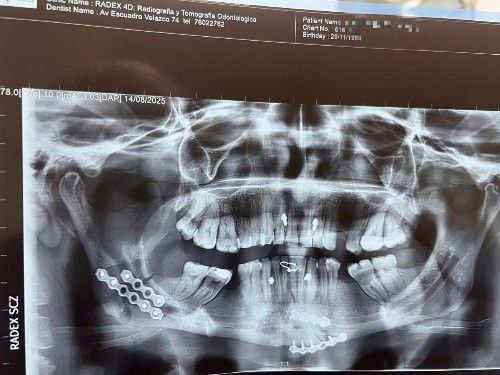

Fractura Facial por Accidente Automovilístico – Cirujano Maxilofacial La Paz (el alto) – Centro de Cirugía Bucal y Traumatología Maxilofacial en Bolivia

Los accidentes de tránsito son frecuentes y la falta de uso de cascos en motocicletas o cinturones de seguridad en automóviles incrementa el riesgo de fracturas faciales. En nuestro Centro de Cirugía Bucal y Traumatología Maxilofacial brindamos atención de emergencia inmediata y especializada. Consúltenos.